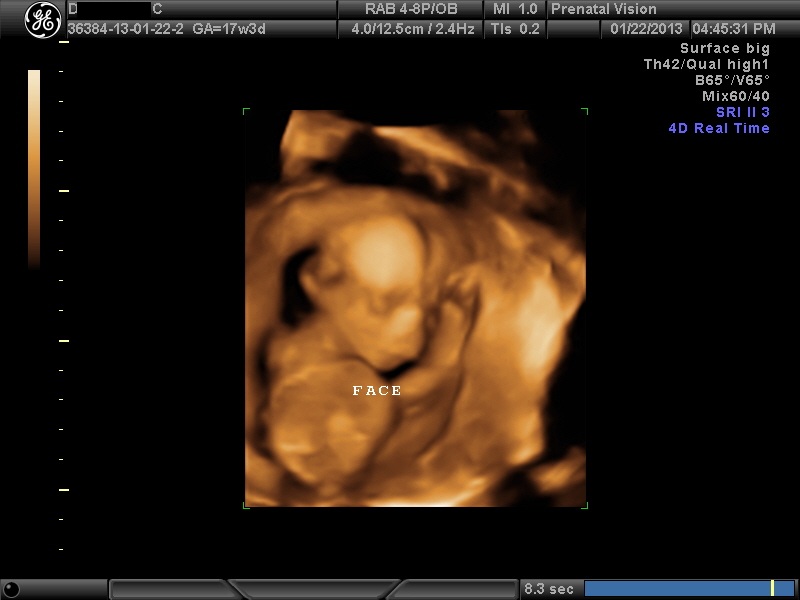

IMAGES_17 January 22, 2013 by Courtney Leave a comment ← Previous Image Next Image → 17w3d – Peeking out for a brief moment Like Loading...